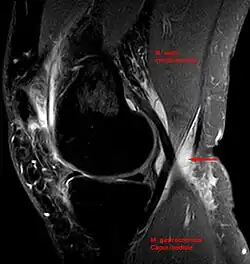

Diagnosis is by examination. A Baker's cyst is easier to see from behind with the patient standing with knees fully extended. It is most easily palpated (felt) with the knee partially flexed. Diagnosis is confirmed by ultrasonography, although if needed and there is no suspicion of a popliteal artery aneurysm then aspiration of synovial fluid from the cyst may be undertaken with care. An MRI image can reveal presence of a Baker's cyst.

Baker's cyst on axial MRI with communicating channel between the semimembranosus muscle and the medial head of the gastrocnemius muscle.